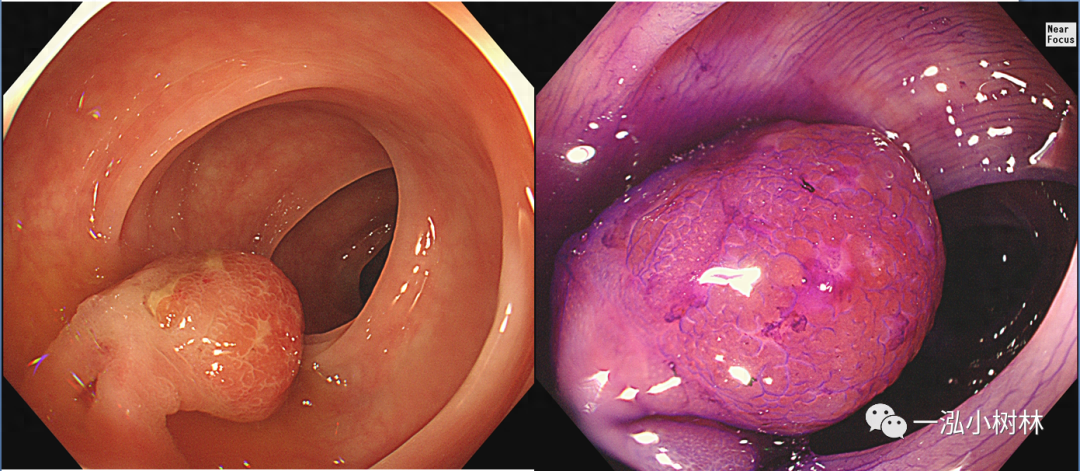

图3 结肠管状腺瘤(Pit Pattern IIIL型)